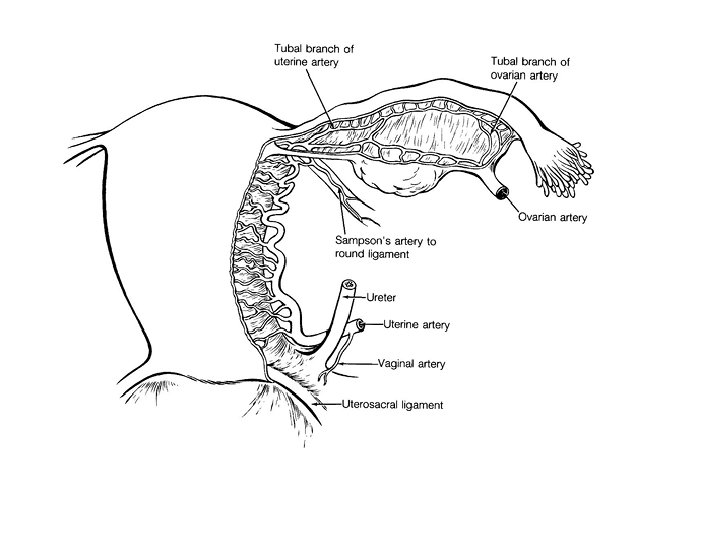

Tuba Uterina (Fallop Tüpleri-Salpinx) • İnfundibulum (fimbria, fimbriae ovarica) pars ampullaris, isthmica, interstitialis • A. ovarica ve A. uterina

Ovaries Medulla (blood and lenf vessels, nerves) Cortex (germinal epitel, tunica albuginea, hilum ovarii) Lig. Ovarii Proprium (between overies and uterus) Lig. Suspensorium Ovarii (infundibulopelvic) (between overies and pelvic side wall) • A. ovarica, plexus pampiniformis • •

Pelvic Vasculature Sakralis Media İnternal iliak (hipogastrik) Common Iliac İliolumbar Lateral Sakral Superior Gluteal Inferior Gluteal Orta Hemoroidal Pudendal Uterin Inferior Vesika Umbilical Obturator Burnett Novack’s Gynecology 20

Branches of the Internal Iliac Artery Anterior Division Posterior Division Uterine Umbilical Uterine vesical Obturator Internal pudendal Inferior gluteal Middle vesical Middle rectal Vaginal Superior gluteal Lateral sacral Iliolumbar

• Ovarian arteries – Originate directly from the aorta, inferior to the renal arteries. – Most frequently identified at the IP ligament. • Ovarian veins: – Left ovarian vein drains into the left renal vein – Right ovarian vein drains directly into the inferior vena cava.

Ligaments of the Uterus • Lig. Sacrouterinum (LUNA) • Lig. Latum Uteri • Lig. Rotundum – Cyst of Nuck canal – A. Sampson – Lig. Cardinale most important lig.